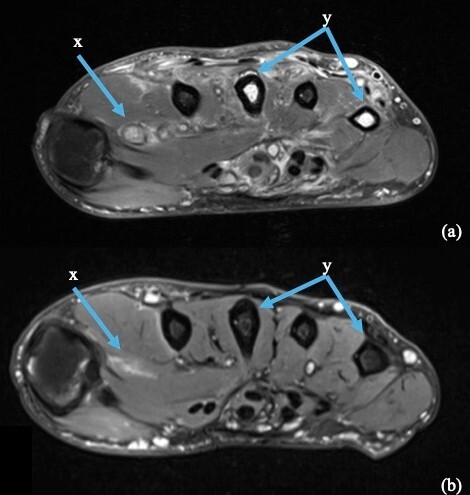

Examination revealed generalised swelling of the entire right hand with multiple small lumps on the volar surface and one sinus on the palm discharging small red grains. There was no cellulitis or tenderness present in the hand (Figure 1). He had a full range of motion and normal sensation in the hand with no lymphadenopathy. Imaging with a CT scan found cortical erosions and cystic changes at the base of the third metacarpal suggestive of osteomyelitis (Figure 2). These soft tissue lesions were shown to be multiple rim-enhancing collections within the intrinsic musculature of the hand, in keeping with infective abscesses on MRI. Imaging also showed erosion of the third metacarpal base, loculated collections around multiple carpometacarpal joints and bony inflammation.

Based on the imaging findings, an excisional biopsy was performed and demonstrated widespread inflammatory changes in the right hand. The granulomatous inflammation communicated from volar to dorsal plate, invading the intrinsic musculature and metacarpals, with macroscopic osteomyelitis of the third metacarpal base. A single discrete lesion that was heavily adherent to the surrounding inflammatory tissue was amenable to excision (Figure 3). Histopathological analysis showed filamentous bacteria which was confirmed to be Actinomadura species on subsequent 16S rRNA testing, but multiple specimens (tissue and bone) sent for culture were all negative.

Following confirmation of relapse of infection and the presence of mycetoma, the patient was referred to the infectious diseases department for targeted antimicrobial therapy. A regimen of trimethoprim/sulfamethoxazole and amoxicillin/clavulanic acid was prescribed. The patient completed a total course of 27 months of antimicrobial therapy and has achieved disease control with resolution of swelling and no palpable subcutaneous nodules on examination (Figure 4). Disease regression was confirmed on MRI with resolution of rim-enhancing collections and only limited bony and soft tissue changes remaining, likely indicative of scarring (Figure 5).